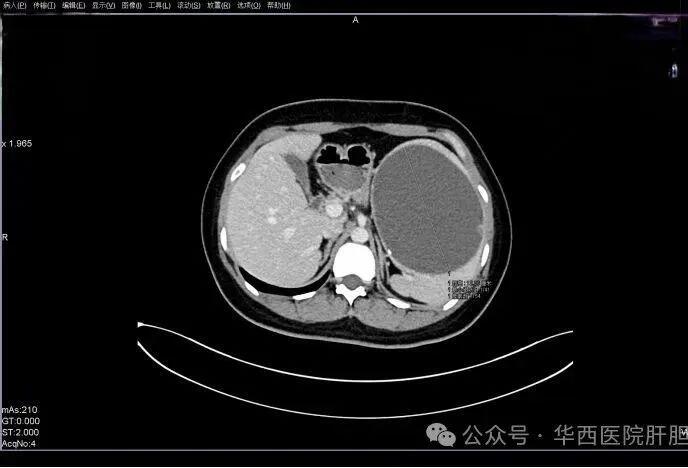

01, 第一例:患者陈某,女,28岁,8+年前患者无明显诱因出现左上腹胀痛,运动后加重。2016年5月于外院行“脾囊肿开窗引流术”症状稍缓解,2019年7月因再发“脾囊肿”于外院行硬化剂注射。近期又出现上腹部胀痛不适,检查发现近 14cm 脾囊肿(从脾下极至上极),遂门诊就诊收治入院。入院后我院彩超提示:脾脏形态失常,内查见大小约 13.6x12.2x9.1cm 的无回声团,边界较清,形态较规则,内透声差,囊壁可见点片状强回声,未见明显血流信号,余脾脏实质回声均匀。

术前CT